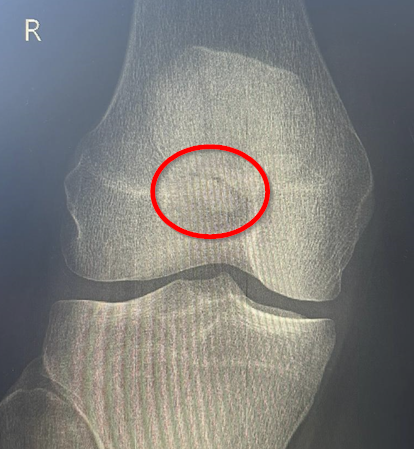

Diese Woche Freitag steht der heiß ersehnte Termin beim Orthopäden an. Das (hoffentlich) letzte Mal röntgen. Wenn ich dort das Okay bekomme, kann es endlich wieder mit dem Laufen und dem Muskelaufbau des rechten Beins los gehen. Momentan ist der Oberschenkelmuskel noch immer eher ein schwabbeliges Etwas und ich freue mich schon darauf, diesen in das zu verwandeln, was er einmal war. Ich bin sehr gespannt, wie der Einstieg ins Laufen klappen wird und wie schnell ich meine Ausdauer wiederaufbauen kann. Ihr werdet es hier auf jeden Fall erfahren!